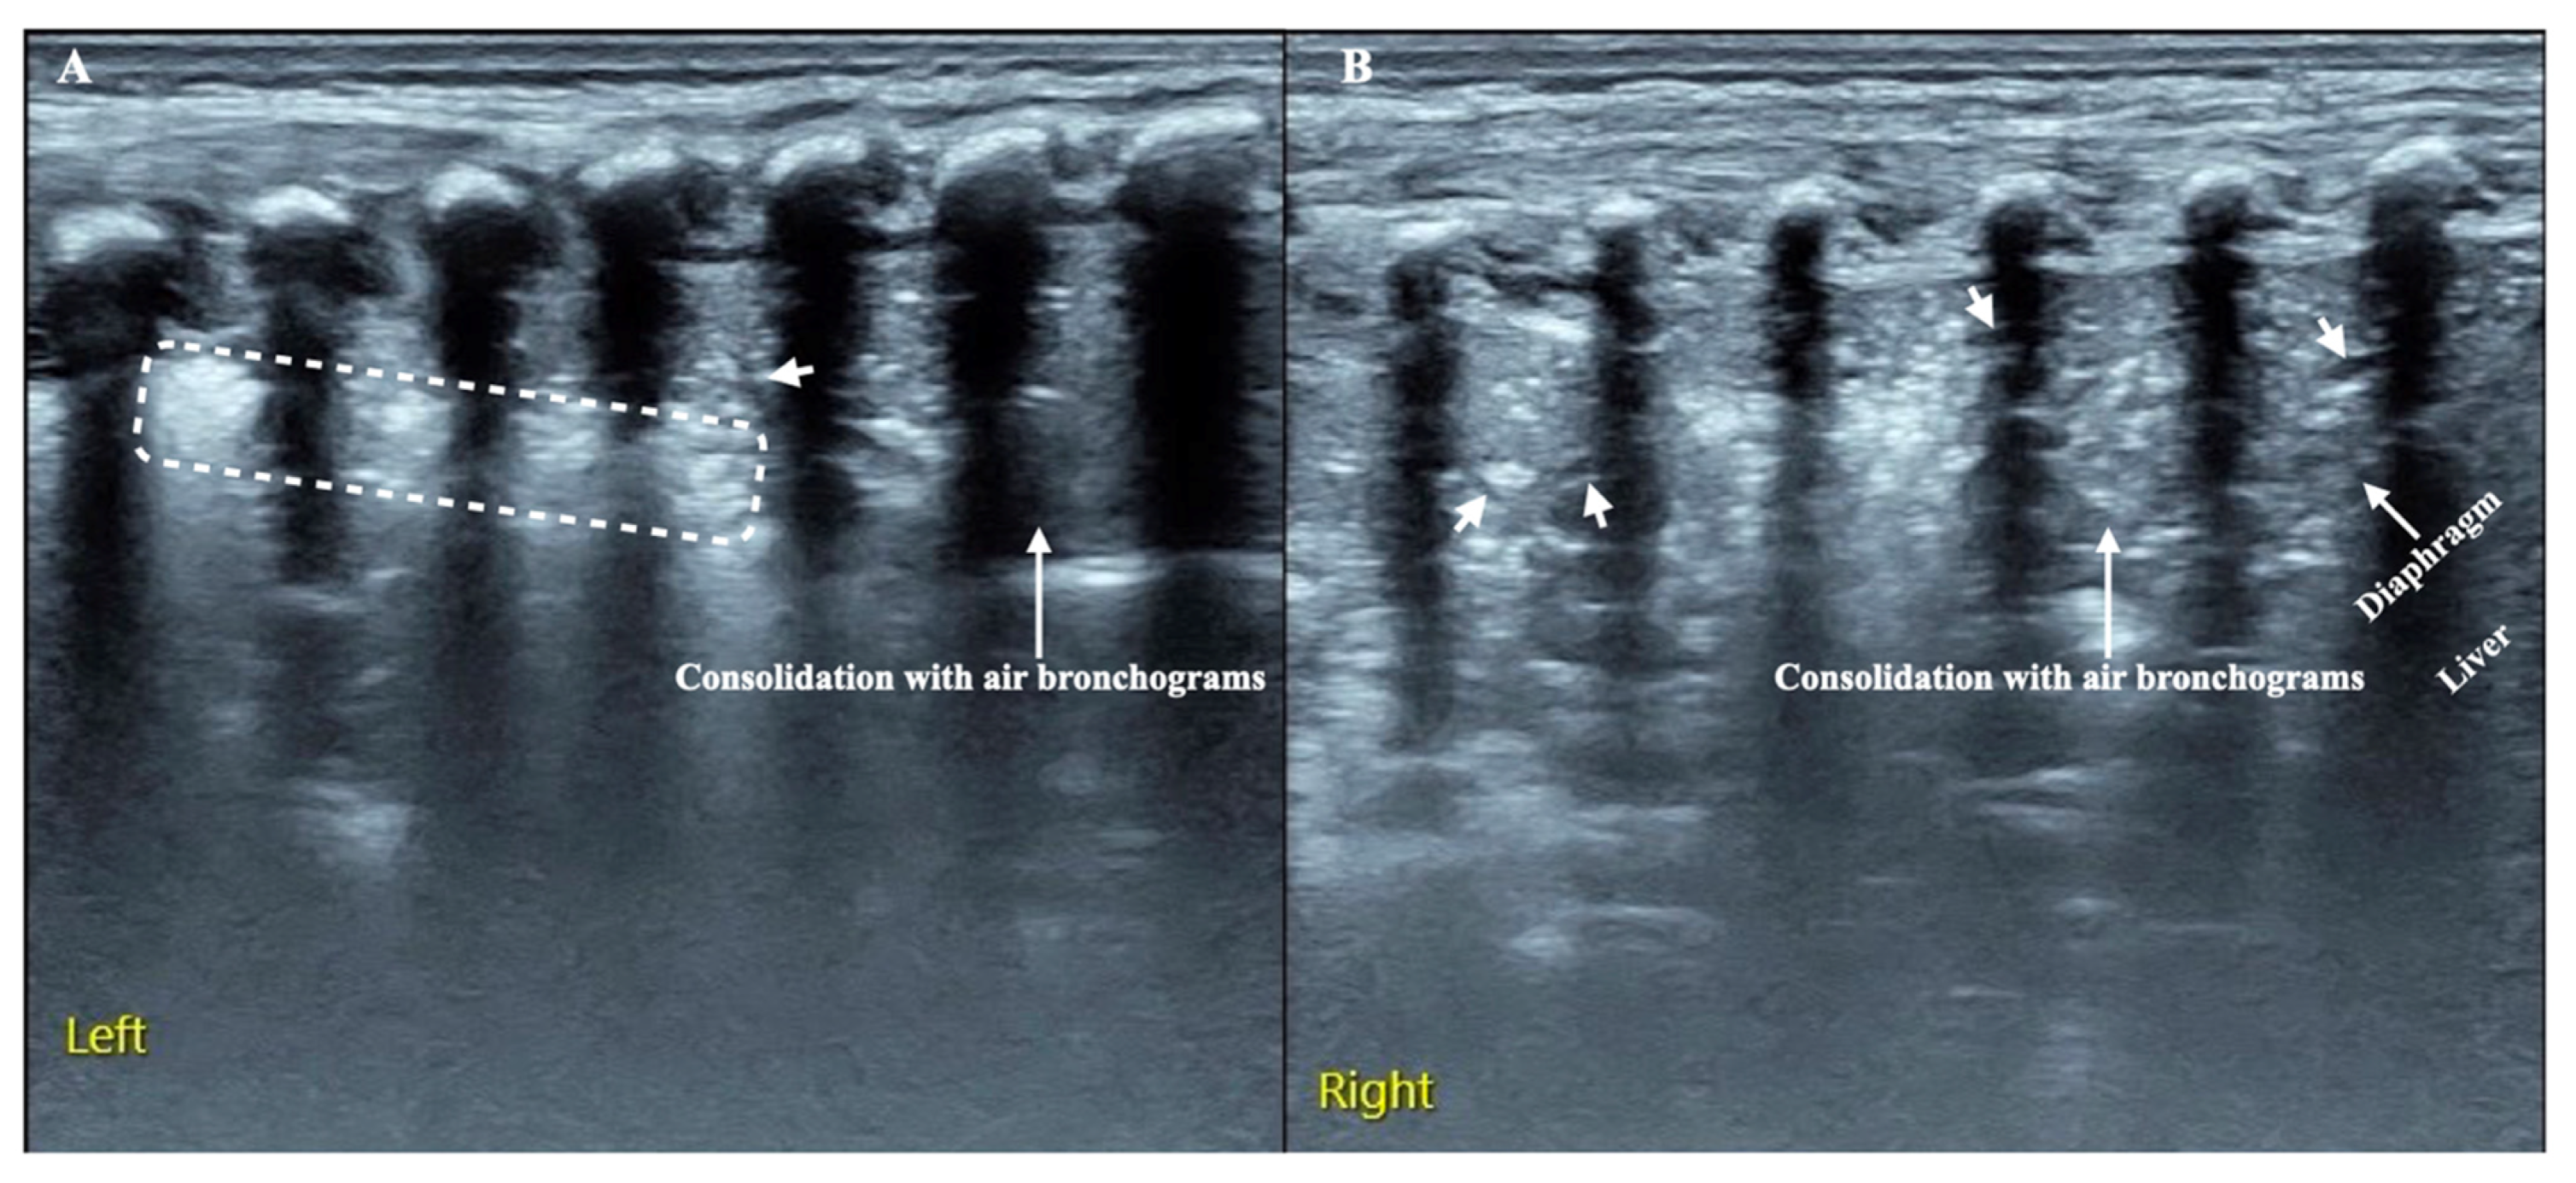

| Consolidation | Area in which lung tissue is de-aerated with density similar to parenchymal tissues [23] |

| Atelectasis | Type of consolidation shown as hyperechogenic tissue structure visualized as solid parenchyma with static air bronchogram [11,24] |

| B-lines | Vertical reverberation artefacts from the pleural line to the edge of the scree; laserlike, vertical hyperechogenic artefacts synchronized with pleural line [11,23,27] |

| Pleural irregularities | Reduction or interruption of pleural line [11,28] |

| Sub-pleural nodes/granularities | Hyperechogenic subcentimetric granularities or consolidation under the pleural line [29,30] |